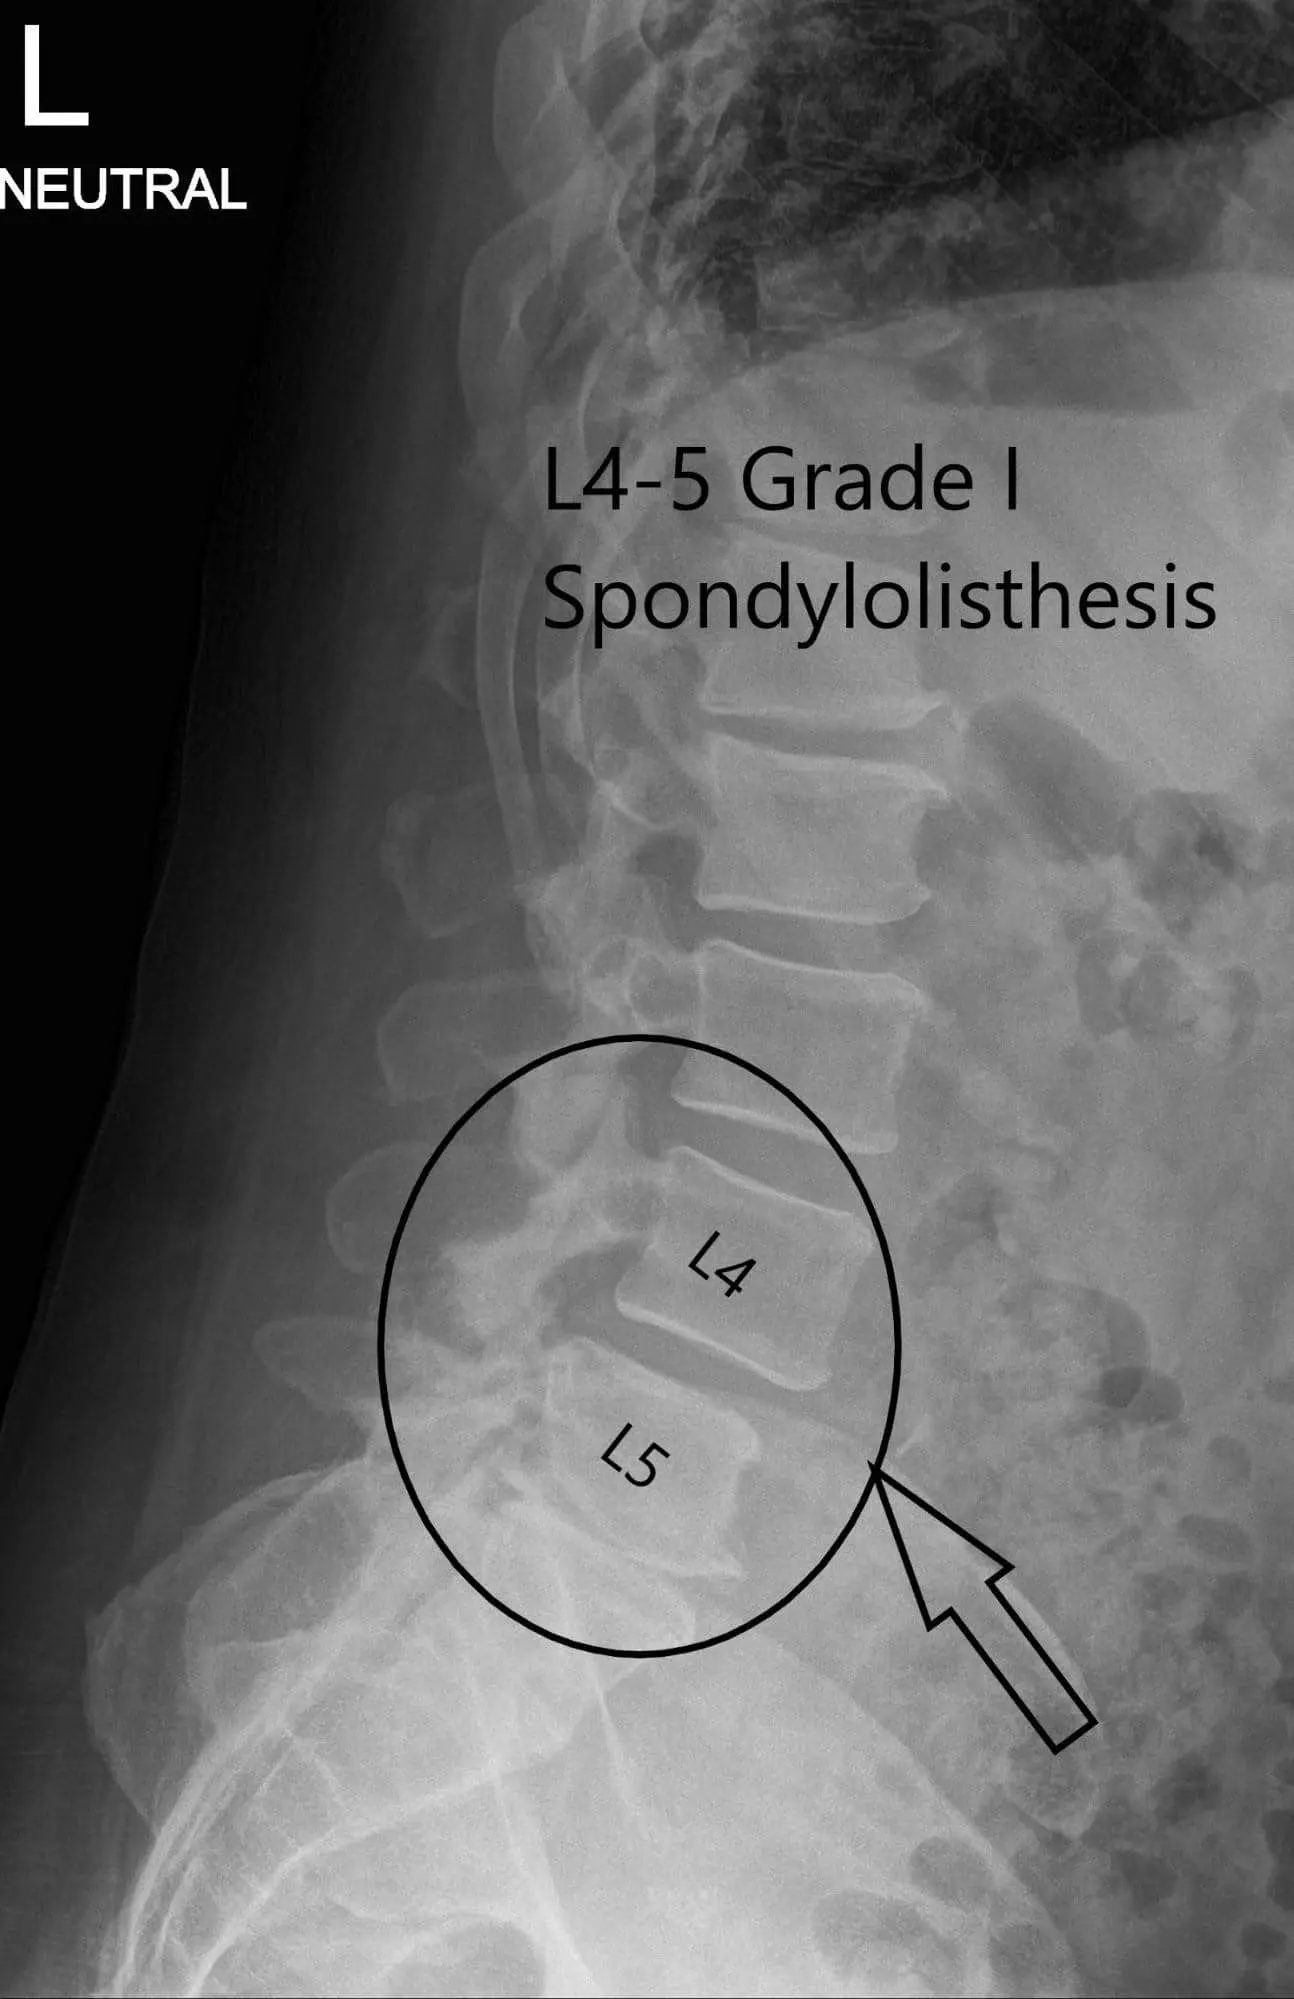

X-ray of the lumbar spine was reviewed with the patient. The X-ray revealed severe degenerative changes at L5-S1 and 5 mm anterolisthesis at L4-5.

Preoperative X-ray LS spine in AP and Lateral Views

Preoperative X-ray LS spine in AP and Lateral Views 2

Preoperative X-ray LS spine in AP and Lateral Views.